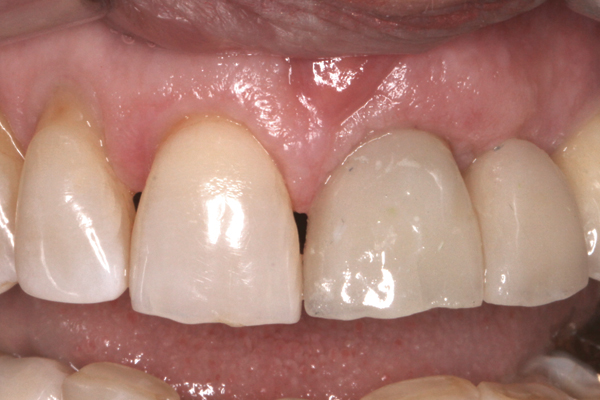

Following the successful integration of implants in the esthetic zone and creation of satisfactory hard- and soft-tissue volume, the restoring clinician is responsible for managing and shaping the definitive soft-tissue architecture. In the esthetic zone, this is a process generally achieved through the use of an implant-retained provisional restoration. The restoring clinician and technician should be intimately familiar with esthetic principles of tooth size, shape, and position. However, the subgingival area of the provisional restoration is also vitally critical. This area, known as the “emergence profile” (Figure 1), plays a significant role in the creation and maintenance of a satisfactory gingival architecture and will ultimately determine the final architecture of the peri-implant soft tissue.

Fig 1. The “emergence profile” is the area of the abutment extending from the head of the implant to the free gingival margin.

Figure 1